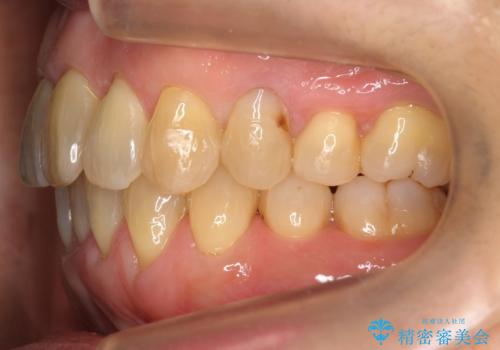

- 前歯のがたつきを主訴に来院。

右下の犬歯が歯ぐきが痩せて、歯肉退縮しておりそれを抜歯しました。

上の前歯はIPRを行なっています。

右下の犬歯の1本抜歯で最小限の抜歯で並べることができました。

奥歯も上下交互になるようにかみ合わせることができました。